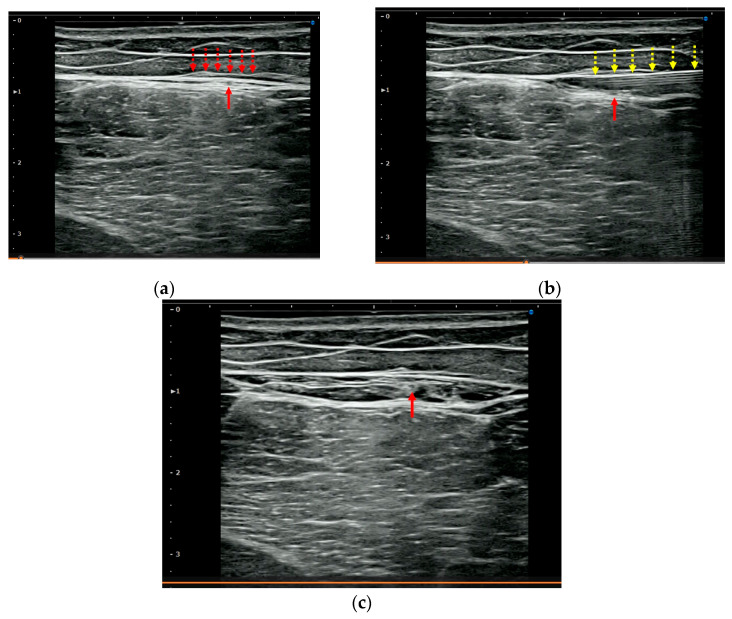

背景:腘绳肌腱损伤后的残余疼痛可能持续存在,尽管肌肉组织愈合并损害运动员寻求早期完全恢复。由于其原因尚不清楚,最近的注意力集中在筋膜功能障碍的作用和恢复筋膜活动的方法,即氢释放(HR),包括超声(US)引导下注射生理盐水。我们评估了HR治疗残余疼痛的临床疗效,并确定了其潜在的病理机制。方法:选取腘绳肌损伤后残余疼痛≥8周的7例患者,年龄17-49岁。所有患者均表现出局部压痛和超声显示腱膜筋膜(APF)周围的筋膜增厚。6.0 mL盐-利多卡因溶液(0.17%利多卡因)进行HR,靶向apf周围疏松结缔组织。采用数值评定量表(NRS)对HR前后疼痛进行评估。被动直腿抬高(SLR)用于评估松紧度。结果:术后NRS评分由10分降至0.86分,差异有统计学意义(p = 0.017)。4名患者需要一次HR会议;其中三个需要两到四个疗程。hr后,所有患者的松紧度均有改善。股后短轴超声显示压痛区APF筋膜增厚,包括股后皮神经(PFCN)。随访期间无不良事件及复发(平均6.6个月)。结论:HR靶向周围pfcn - apf可有效减轻腘绳肌损伤后的残余疼痛。这些发现支持了“神经周围筋膜疼痛”的概念,即持续性疼痛不是源于直接的神经损伤或经典的肌筋膜疼痛综合征,而是源于周围筋膜的功能障碍。

Background: Post-hamstring-injury residual pain may persist despite muscle-tissue healing and impairs athletes seeking early full recovery. Given their unclear cause, recent attention has focused on the role of fascial dysfunction and a method to restore fascial mobility, namely, hydrorelease (HR), involving the ultrasound (US)-guided injection of saline. We evaluated the clinical efficacy of HR for treating residual pain and ascertained the underlying pathological mechanisms. Methods: Seven patients (aged 17-49 years) with residual pain ≥8 weeks after hamstring injury were included. All exhibited localized tenderness and US findings of fascial thickening around the aponeurotic fascia (APF). HR with 6.0 mL saline-lidocaine solution (0.17% lidocaine) was performed and targeted the peri-APF loose connective tissues. Pain was evaluated using a numerical rating scale (NRS) before and after HR. Passive straight leg raise (SLR) was used to assess tightness. Results: Post-HR, the mean NRS score significantly decreased from 10 to 0.86 (p = 0.017). Four patients required a single HR session; three required two-four sessions. Post-HR, the tightness of all patients improved. Short-axis US of the posterior thigh revealed APF fascial thickening in the area of tenderness, including the posterior femoral cutaneous nerve (PFCN). No adverse events or recurrence occurred during the follow-up (mean: 6.6 months). Conclusions: HR targeting the peri-PFCN-APF effectively reduced residual pain following hamstring injury. These findings support the concept of "Perineural fascial pain"-a pathology wherein persistent pain originates not from direct nerve damage or classical myofascial pain syndrome but rather from the dysfunction of the surrounding fascia.